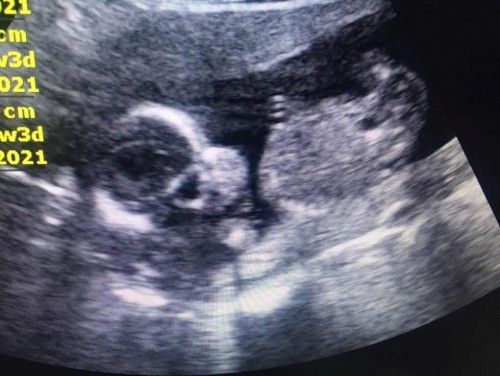

21 มกราคม ตอนนี้ 29w+1d ค่า